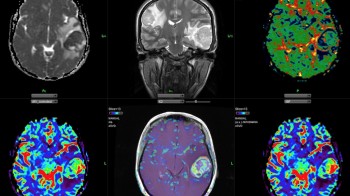

MRI mozga / glavobolje, upale , tumori, drugo

MRI pregled mozga je najbolja metoda za analizu mozga, njegove bijele I sive mase, bilo da se radi o upalnim, tumorskim, autoimunim ili drugim stanjima. Nema štetnog jonizujućeg zračenja a nezamjenjiva je metoda za dijagnostiku sekundarnih glavobolja, odnosno oboljenja koja uzrokuju glavobolje. Zajedno sa MRA-magnetnom angiografijom-pregledom krvnih žila mozga- dobija se vrhunsko slikovno stanje endokranijuma.